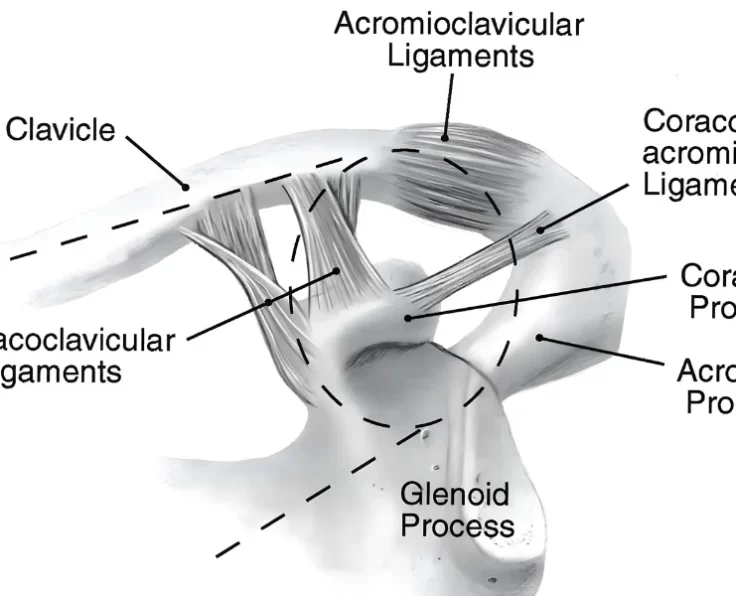

AC Joint Reconstruction

The acromioclavicular joint, often known as the AC joint, is positioned on the top of the shoulder, where the clavicle (collarbone) meets the acromion (shoulder…

AC Joint Excision

The goal of the procedure is to remove the uncomfortable and injured Acromioclavicular Joint (ACJ) without causing it to become unstable.